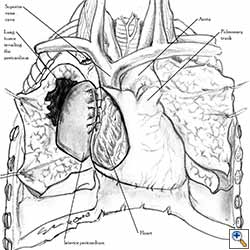

Pericardial reconstruction after anterior mediastinal tumor resection

Some pericardial defects resulting after partial pericardiectomy for invasive anterior mediastinal masses need pericardial reconstruction (Figures 4a-c). This is not the case for small pericardial defects, but large and lateral defects require reconstruction, especially if a lung resection has been performed. In the case of pericardiectomy with pneumonectomy, the postpneumonectomy space plays an important role in the pathogenesis of cardiac herniation. En bloc resection of a mediastinal tumor, the pericardium and the lung increases the risk of herniation in a similar fashion. In the absence of a lung resection, lung atelectasis can also increase this risk. Following complex resections requiring vascular resection followed by reconstruction, the reconstruction can stabilise the vascular prosthesis and prevent it from kinking (Figure 4c). Another potential advantage of pericardial reconstruction is that in the event of a re-do sternotomy, the risk of cardiac laceration is reduced because it prevents sternal-cardiac adhesions from forming [5]

| Figure 8a: Sutures are placed through the pericardial edges of the anterior defect. | Figure 8b: The mesh is fixed with the sutures. | Figure 8c: Final aspect of the anterior pericardioplasty. |

|

Video 1 depicts a pericardial reconstruction with Marlex after a right completion pneumonectomy with pericardiectomy for lung adenocarcinoma (see also Figure 1). The technique of pericardial reconstruction after the resection of invasive mediastinal tumours is illustrated in Figures 8a-c). Video 2 depicts a pericardial reconstruction with Mersilene mesh after the resection of a malignant thymoma invading the anterior pericardium (see also Figure 4b). The technique of right pericardial reconstruction after extrapleural pneumonectomy is illustrated in Figures 9a and 9b). Video 3 depicts a pericardial reconstruction using Gore-Tex Dual Mesh after a left extrapleural pneumonectomy (see also Figure 3). Care must be taken to prevent constriction (Figure 10).